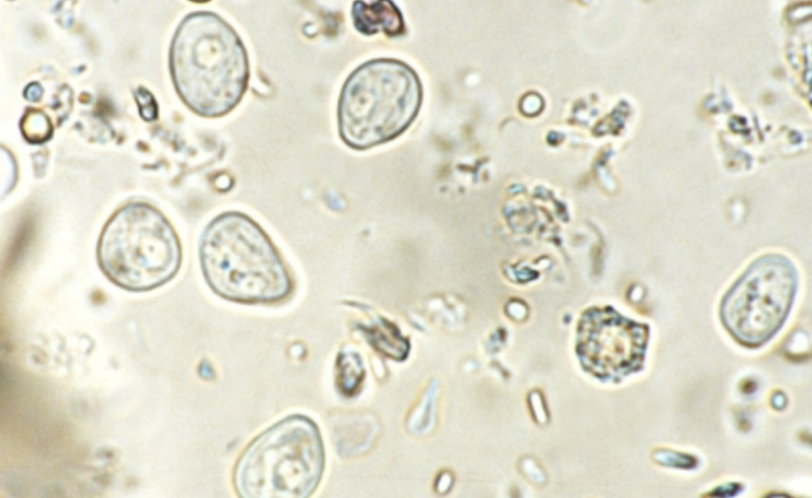

Giardia duodenalis (cyst)

Giardia duodenalis (cyst)

Giardia duodenalis (troph)

Giardia duodenalis (troph)